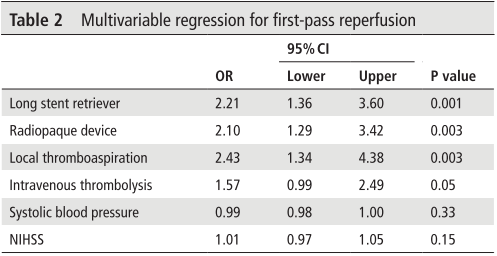

该病例是心源性栓塞,血栓质韧,本例选用蛟龙4*30mm更长的取栓支架,更长长度提供更大表面积接触血栓,以独特的侧边螺旋开放结构,帮助快速高效一次三级再通。一篇研究回顾性分析了2011年6月到2017年3月使用直径4mm取栓支架及球囊指引导管作为首选治疗策略治疗ICA、MCA急性闭塞的病例。该研究中,4×30mm和 4×40mm被定义为长支架,4×20mm被定义为短支架。主要的临床结局是一次性取栓血管成功再通率(mTICI 2b/3)。研究共纳入420例患者,其中221例(53%)患者使用长支架,119例(47%)使用短支架。相对于短支架,长支架组一次性取栓血管开通率(62% vs 50%;P=0.01)和最终血管开通率(mTICI2b/3,98% vs 94%;P=0.01)更高。长支架一次性取栓成功开通率高的原因,可以从以下几方面来解释:长血栓会提供更大的表面积与取栓支架接触包裹血栓,也会在取栓过程中使张力均匀分布,在血管路径扭曲或者躁动的病人中,长支架通过增加可接受的误差范围来实现精确释放。更长的支架会增加取栓装置向血栓远端延伸的移动力,同时,在支架首个与血栓接触的网孔抓捕血栓失败的情况下,可以增加血栓取出的机会。[1]因此,通桥医疗即将上市的蛟龙4*30mm取栓支架在临床上的广泛应用值得期待。